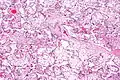

Micrograph of villous immaturity. H&E stain. | |

Placental villous immaturity is chorionic villous development that is inappropriate for the gestational age.

Immature chorionic villi are larger and have more central blood vessels; thus, the diffusion distance for gas and nutrient exchange is larger and, therefore, placental function is impaired.

- High mag.